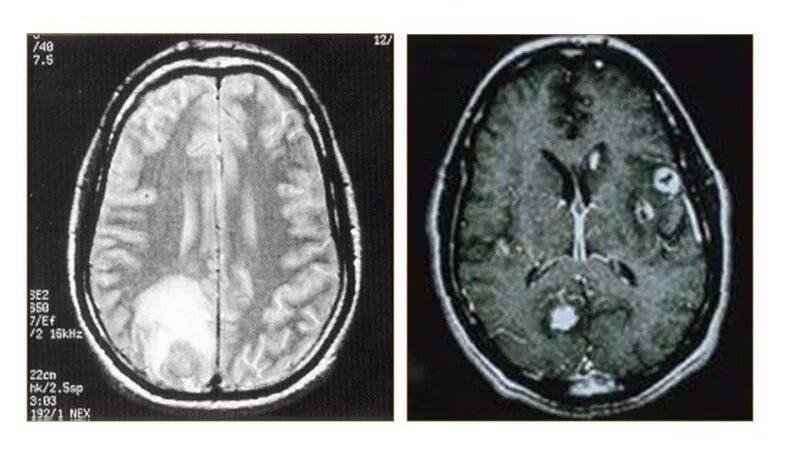

Токсоплазмоз у вич инфицированных